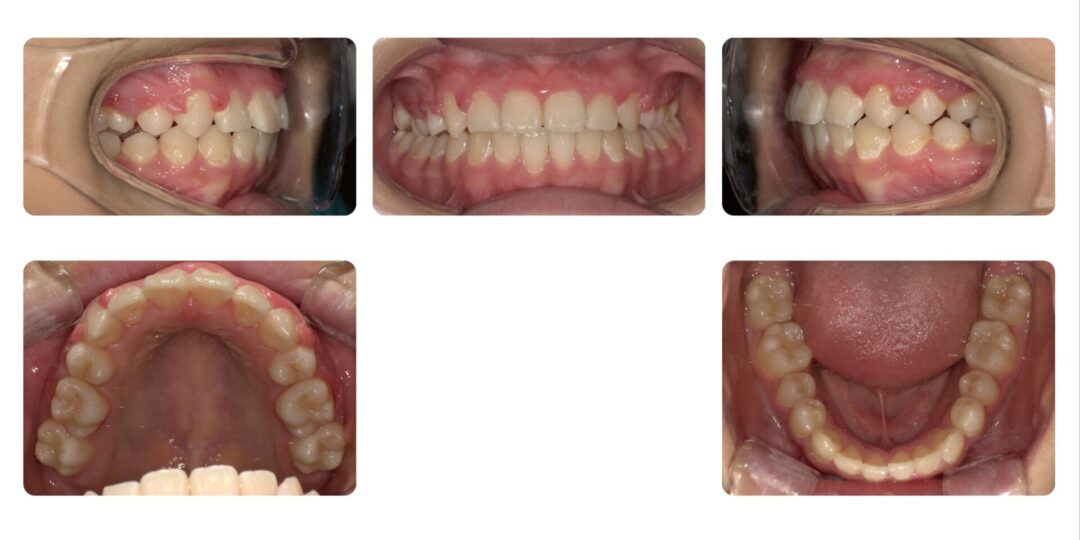

矯正治療後

成人矯正 上顎左右第一小臼歯抜歯 マルチブラケット矯正

2年10ヶ月